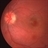

- macular hole, trauma, traumatic macular hole, full thickness macular hole

Fundus camera

Topcon VT-50 - Description

- 14-year-old white male with a traumatic macular hole OS 23 days post hockey puck injury; V.A.= 20/200.